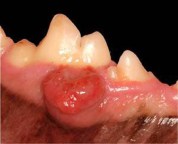

Disa qen dhe mace zhvillojnë rritjen e disa masave ne gojën e tyre.Të ngjashme me njerzit , keto rritje mund të jenë tumore beninj apo malinj.Kur vihet re një masë e tillë analizat janë të nevojshme për të përcaktuar shkakun e rritjes.

Disa masa janë për shkak të infeksioneve në mishrat e dhëmbëve ose të vetë dhëmbit. Shumica shkaktohen për shkak të tumoreve.Disa rraca janë më të predispozuara ndaj rritjes se tumoreve ne gojë( psh; Cocker Spanielët e zinj janë të prirur per melanoma në gojë)

Qentë/macet kryesisht nuk tregojnë shënja të rritjes së këtyre masave në gojë për deri sa rriten aq sa pengojnë përtypjen e ushqimit apo gëlltitjen.Në disa raste mund të kenë frymë të keqe, jargëzim të tepruar me /apo jo gjak .

Veterineri mund të marrë një kampion të qelizave nga masa dhe të përgatisë një lamë mikroskopike për të krijuar një ide nëse kemi të bejmë me infkesion apo tumor.Në shumë raste masa hiqet dhe mund të dergohet ne laborator për analiza më të detajuara.

Pacientët qe kanë tumore jo malinj zakonisht kurohen me anën e heqejs se tumorit në rrugë kirurgjikale. Tumoret malinj kanë nevojë zakonisht per një operacion më “agresiv” dhe kimoterapi për të ulur përhapjen e tumorit.